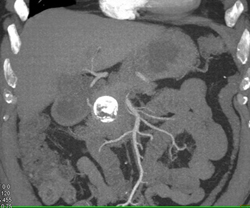

Pseudocyst